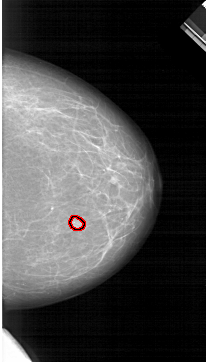

A_1264_1.RIGHT_MLO

RIGHT_MLO LINES 6706 PIXELS_PER_LINE 3631 BITS_PER_PIXEL 12 RESOLUTION 43.5 OVERLAY

FILE: A_1264_1.RIGHT_MLO.OVERLAY

TOTAL_ABNORMALITIES 1

ABNORMALITY 1

LESION_TYPE MASS SHAPE OVAL MARGINS CIRCUMSCRIBED

ASSESSMENT 3

SUBTLETY 4

PATHOLOGY BENIGN

TOTAL_OUTLINES 1

BOUNDARY